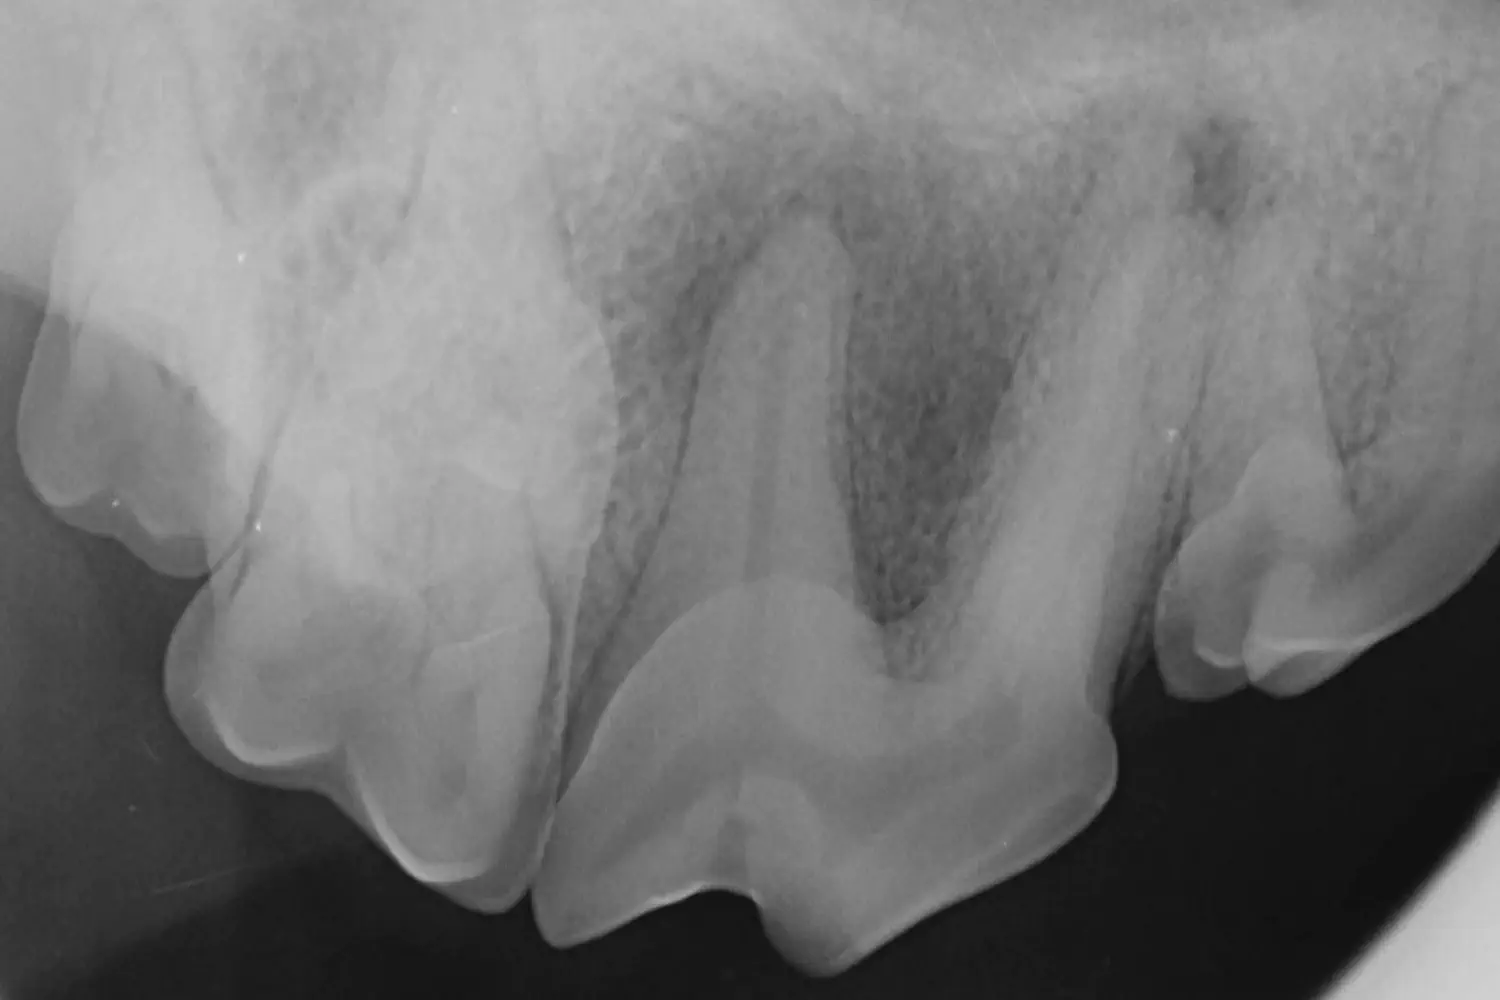

Hammasröntgen

Hammasröntgentutkimus on oleellinen osa hammashoitoa. Hammasröntgenillä nähdään myös hampaiden juurialue ja hampaiden sisäosien rakenteita. Noin kolmannes löydöksistä näkyy vain röntgenkuvissa. Hammasröntgentutkimus tukee hammastarkastuksen löydöksiä, jolloin saadaan kattava ja kokonaisvaltainen tieto suun tilanteesta ja voidaan tehdä yksilöllinen hoitosuunnitelma.

Loistossa on käytössä lisäksi kartiokeilatietokonetomografia (CBCT), joka antaa tarkan kolmiulotteisen kuvan suun luisista rakenteista. CBCT-kuvien avulla voidaan tarvittaessa parantaa diagnostiikkaa.